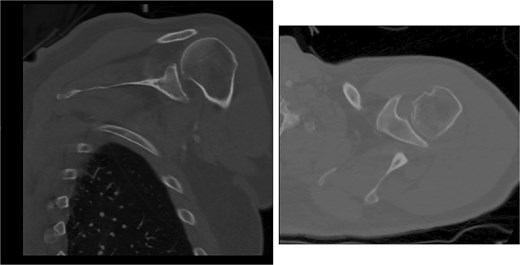

Both shoulders were reduced urgently by the orthopedic team, with immediate improvement in paresthesias (Fig. 2). Post-reduction CTs were significant for bilateral chronic rotator cuff disease with superior migration of the humeral heads, right-sided supraspinatus and subscapularis atrophy, and a left nondisplaced glenoid fracture (Figs 3 and 4). He was discharged home in bilateral slings.

Post-reduction CT of the left shoulder demonstrating superior humeral head migration relative to the glenoid.